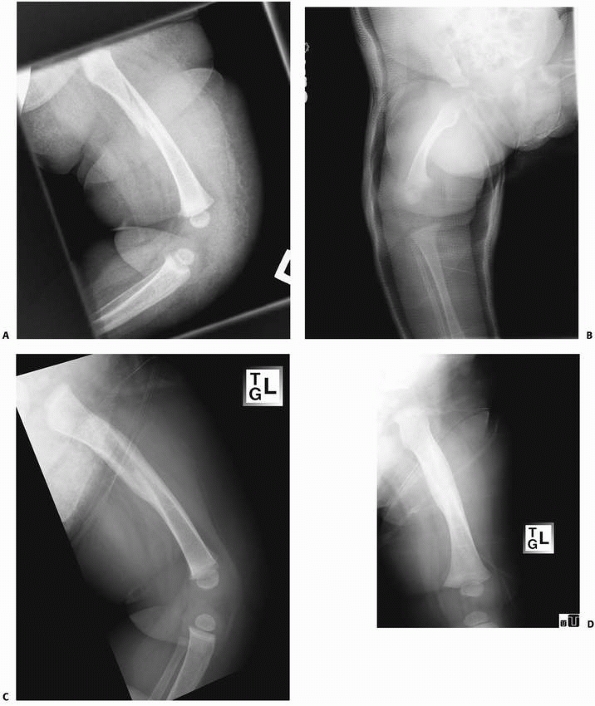

![]() |

FIGURE 22-4 A. This 7-month-old sustained a low-energy spiral femoral shaft fracture. B. Treatment was in a spica cast. C,D. Excellent healing with abundant callus at only 4 weeks after injury.

FIGURE 22-5 A. This 2-year-old sustained a low-energy spiral femoral shaft fracture, ideal for walking spica treatment. B. Immediately after reduction; note the lateral mold at the fracture site. C. Six weeks after injury, there is anatomic alignment, minimal shortening, and good callus formation.